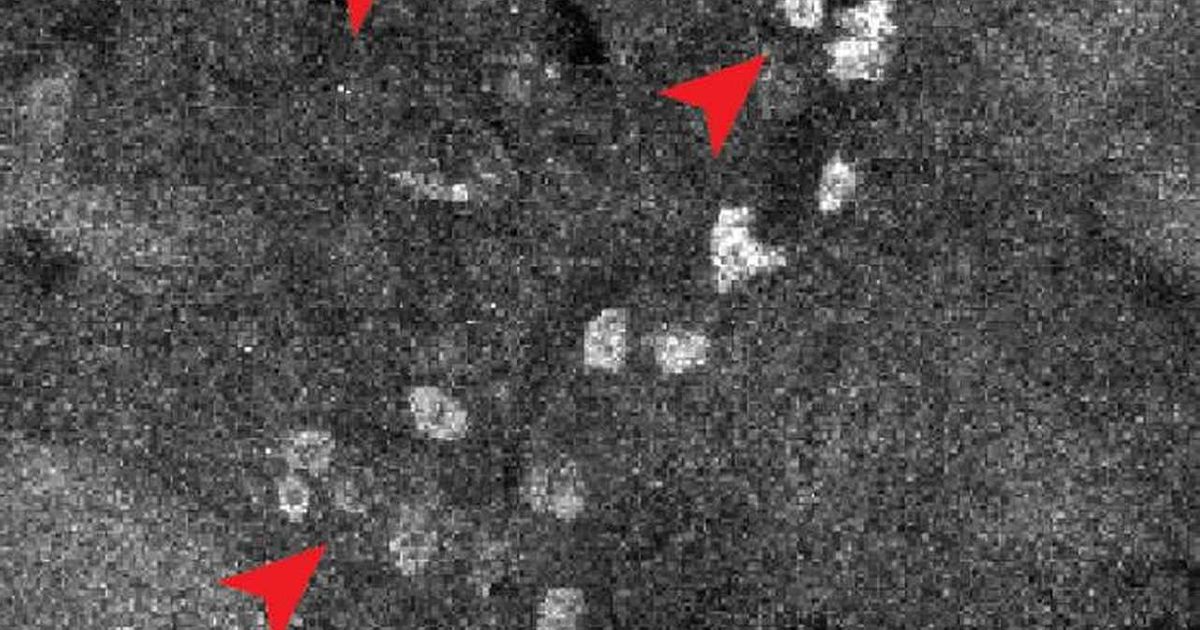

Naučnici iz Istraživačkog instituta Skrips razvili su tehniku koja mapira vezivanje lekova u individualnim ćelijama širom čitavog tela, potencijalno.